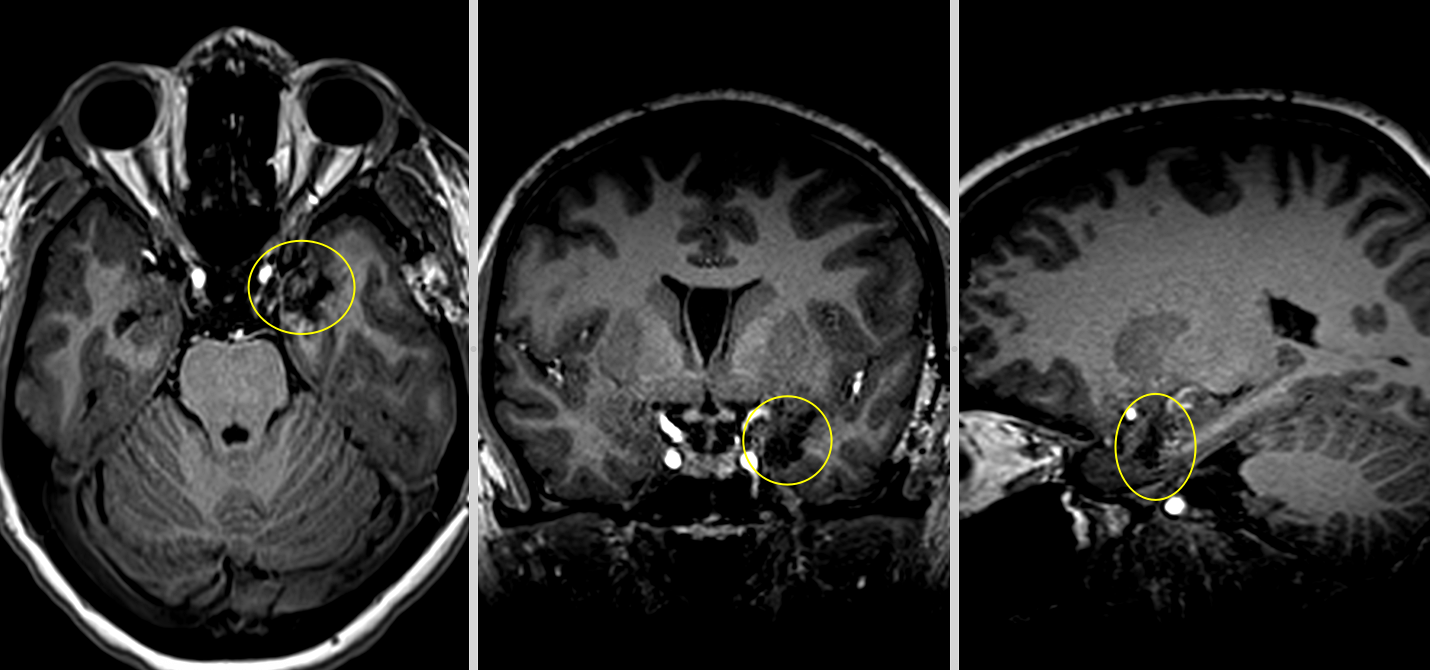

Investigațiile următoare, întâi peste 3 luni apoi peste încă un an au confirmat: nici o urmă de rest sau recidivă tumorală.

La aproape 3 ani de la operație, fără crize epileptice, fără deficite neurologice și cu un RMN curat putem considera că pacienta este vindecată.